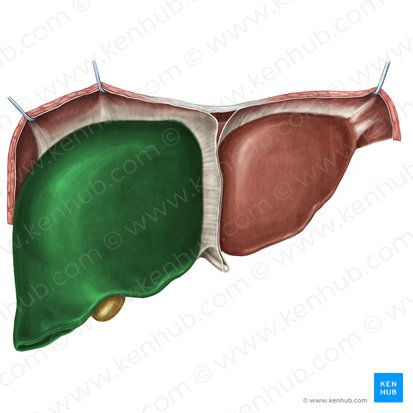

Right lobe of Liver

The larger of the two main lobes of the liver, located on the right side of the abdomen.

Left lobe of the Liver

The smaller of the two main lobes of the liver, located on the left side of the abdomen.

Falciform Ligament of the Liver

A broad, thin fold of peritoneum that attaches the liver to the anterior abdominal wall and diaphragm. It also marks the division between the right and left lobes on the anterior surface.